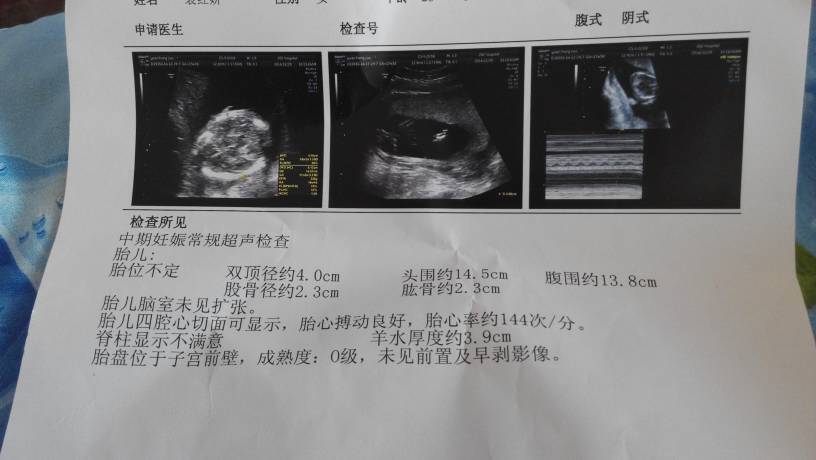

你这个是四个月多点吧?你胎心在这阶段只有144,双顶径与股骨就已经相差1.7,所以男孩的几率大!